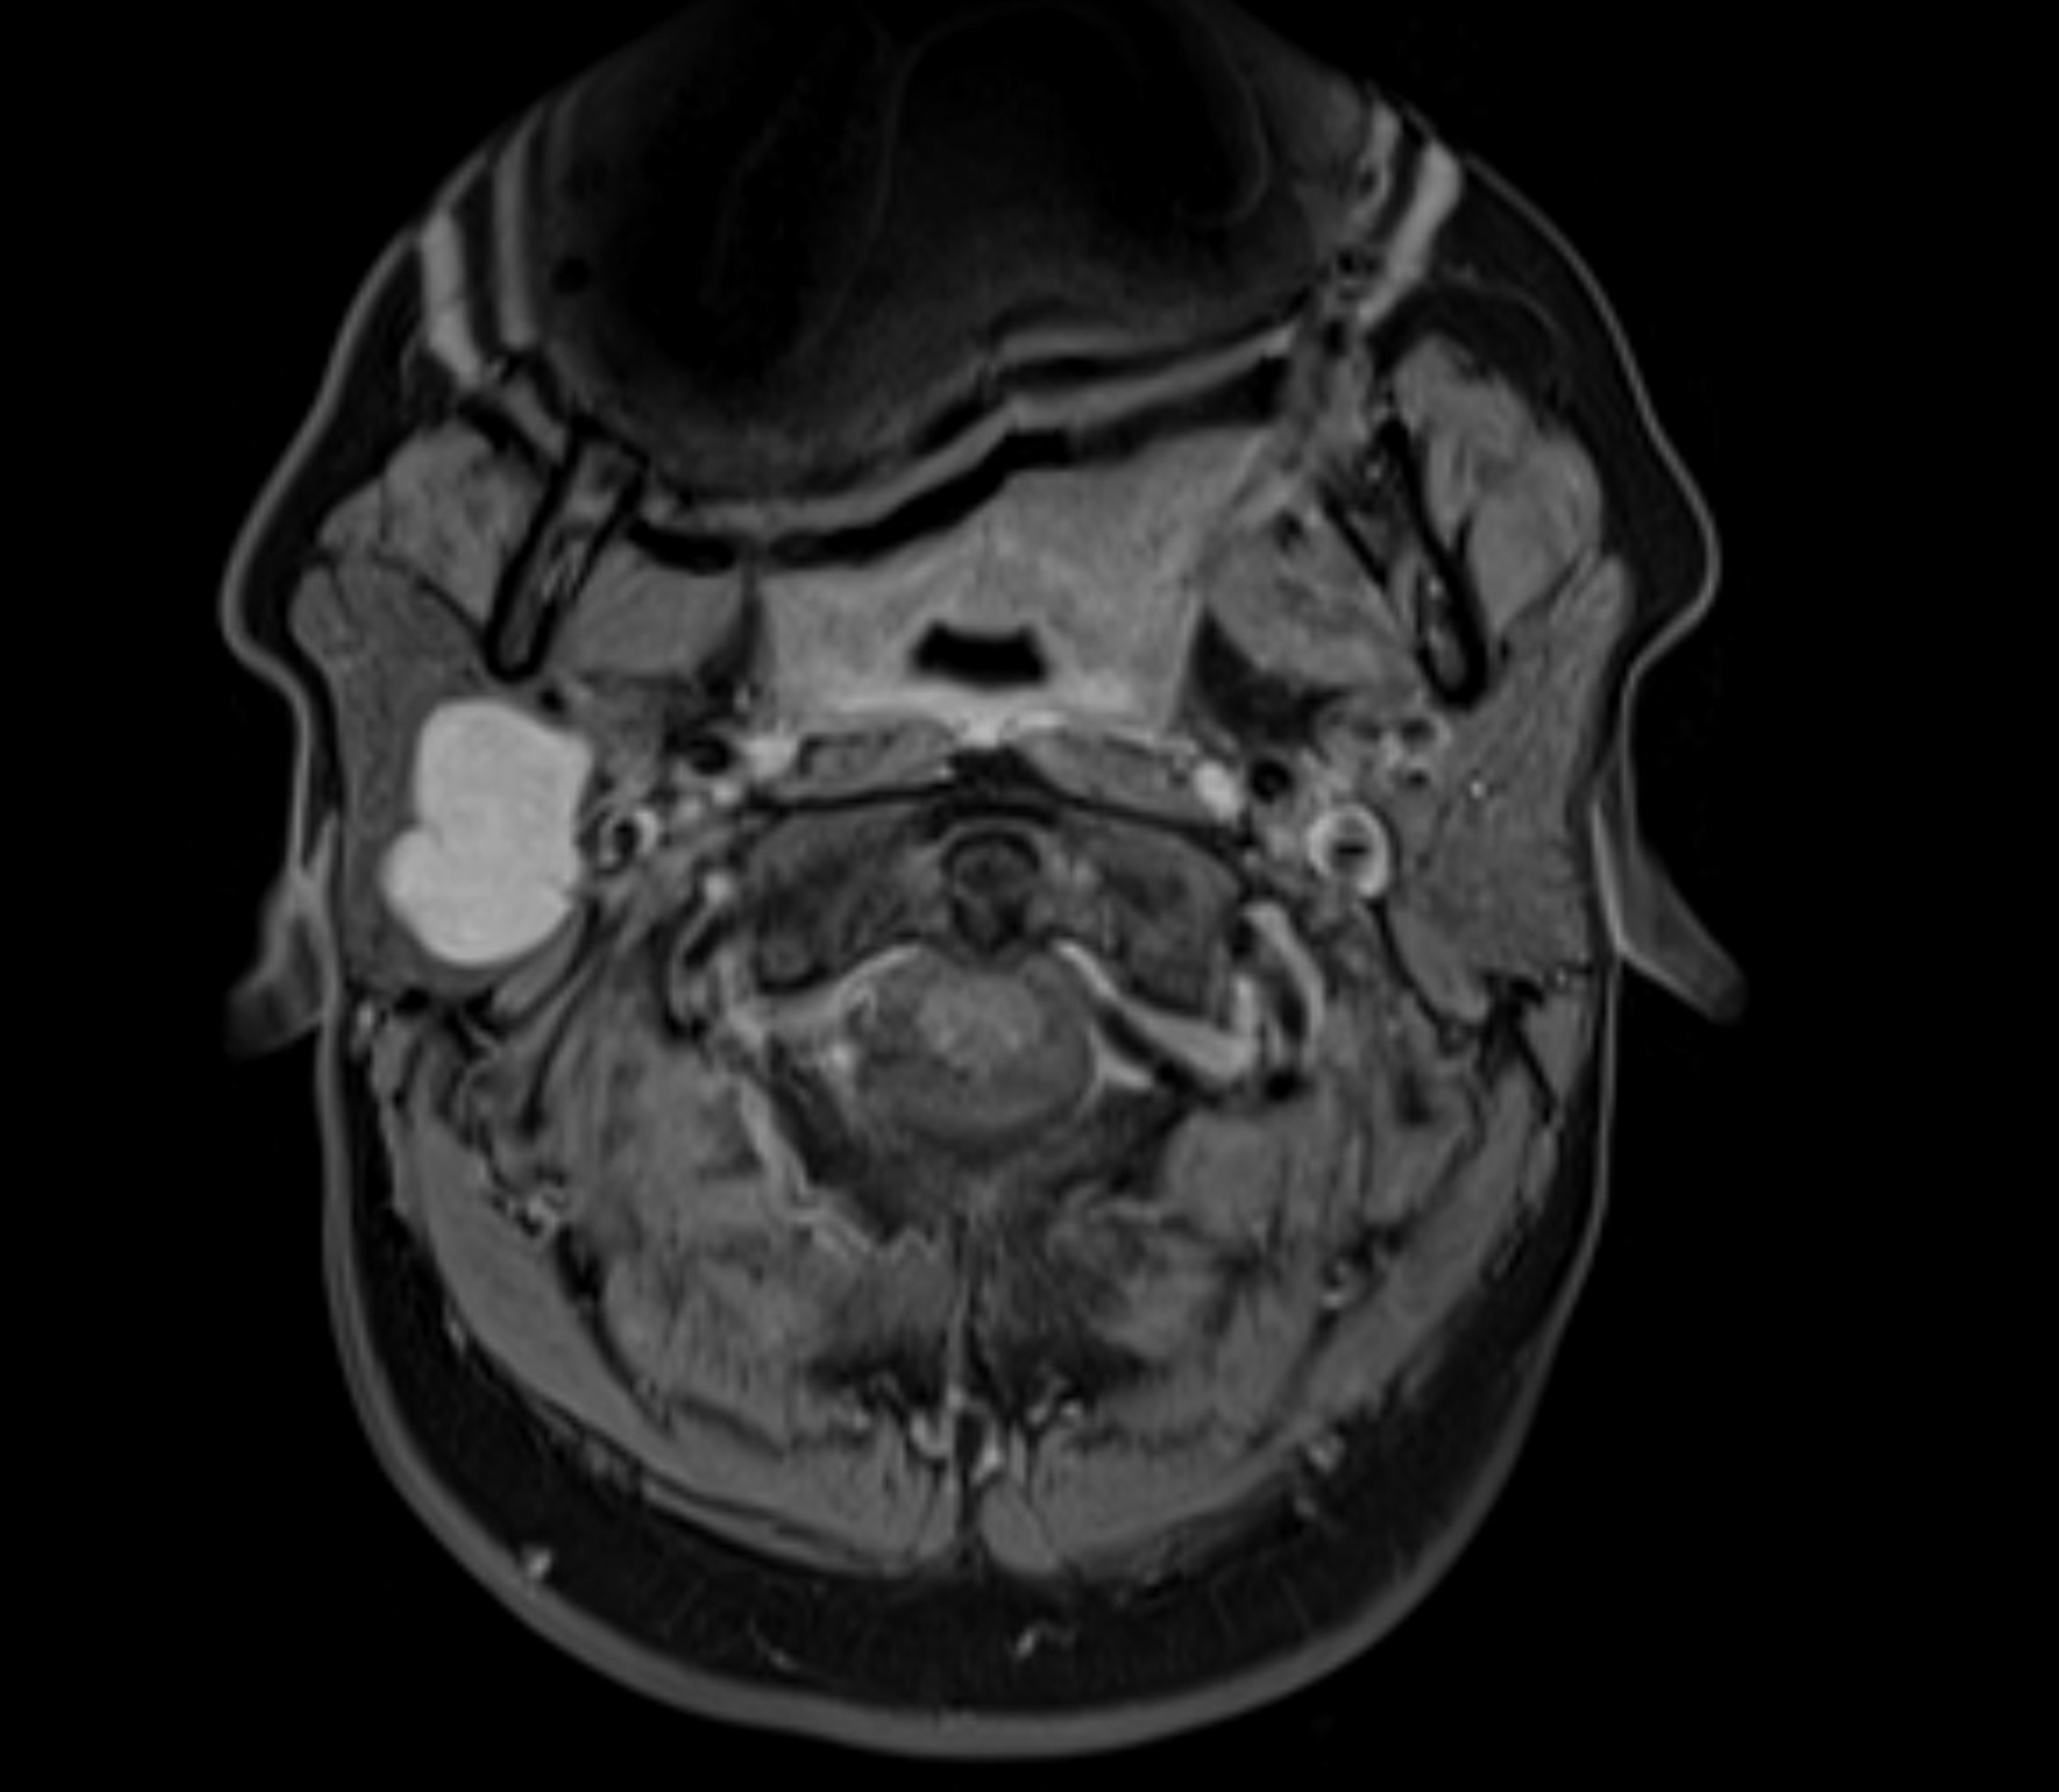

IRM multiparamétrique axiale montrant une tumeur de la glande parotide | Source : Getty Images